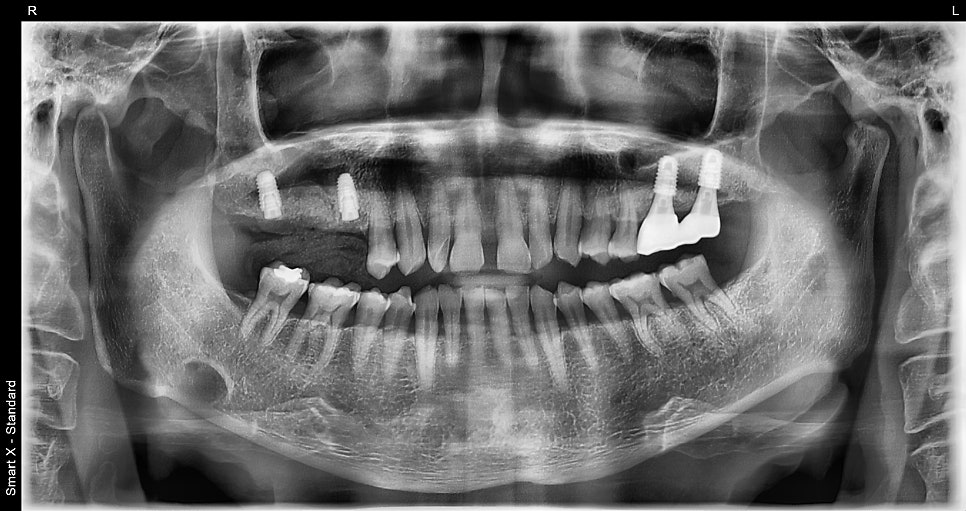

- 1월 초: 오른쪽 염증심한 치아 발치 후 즉시 임플란트 식립 (#17 #15 두개 식립 / 동종골 뼈이식)+ 전체 잇몸 치료 병행 (잇몸 염증 및 골소실 예방 목적)

#16(오른쪽 위 첫번째 큰 어금니), #15(오른쪽 위 두번째 작은 어금니) 발치 후 즉시 임플란트를 식립한 파노라마 엑스레이입니다.

흡연자 특성을 고려해 골유착 속도가 빠를 수도 있지만, 잇몸 상태와 전신질환(고혈압, 당뇨 등)을 고려하여 안전하게 1차/2차로 수술을 나눠 진행했습니다.

※ 필요 시에는 발치 당일 힐링 어버트먼트를 함께 연결해 크라운을 더 빠르게 완성하는 것도 가능합니다.